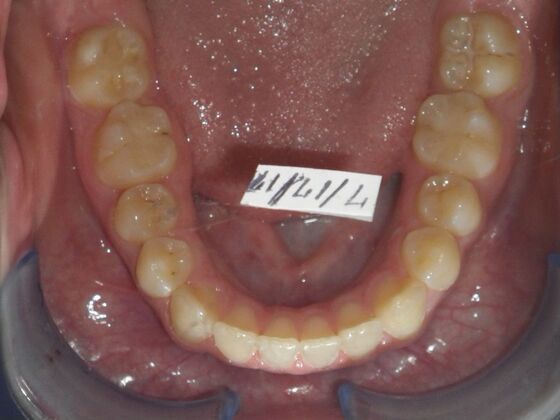

Orthodontics: Case 10

Description

This case presents with a dental midline discrepancy. The upper incisors are tipped toward the palate, which prevents the lower incisors from establishing proper arch form. The upper right molar has drifted forward, causing the upper midline to be skewed to her left. By distalizing the upper left molar, we can correct the midline discrepancy. Lastly, both upper and lower arches need expansion. All of this was completed with conventional straight wire appliances within 2 years.